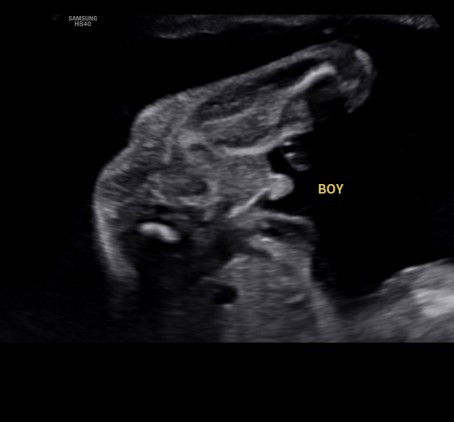

23 weeks gender reveal

Ikut pengalaman mommies ni confirm boy ka?? Sbb rmai ckp perut mcm girl..blh kata smua yg jumpa akn ckp baby girl ya😂 #firstmom

It's crystal clear boy. Yang cakap ikut bentuk perut yada yada tu, awak abaikan je. Kalau tak yakin dengan sono/doktor awak, boleh repeat scan.

Baby boyy terang sgt dh pistolnya tuu..tahniaahh